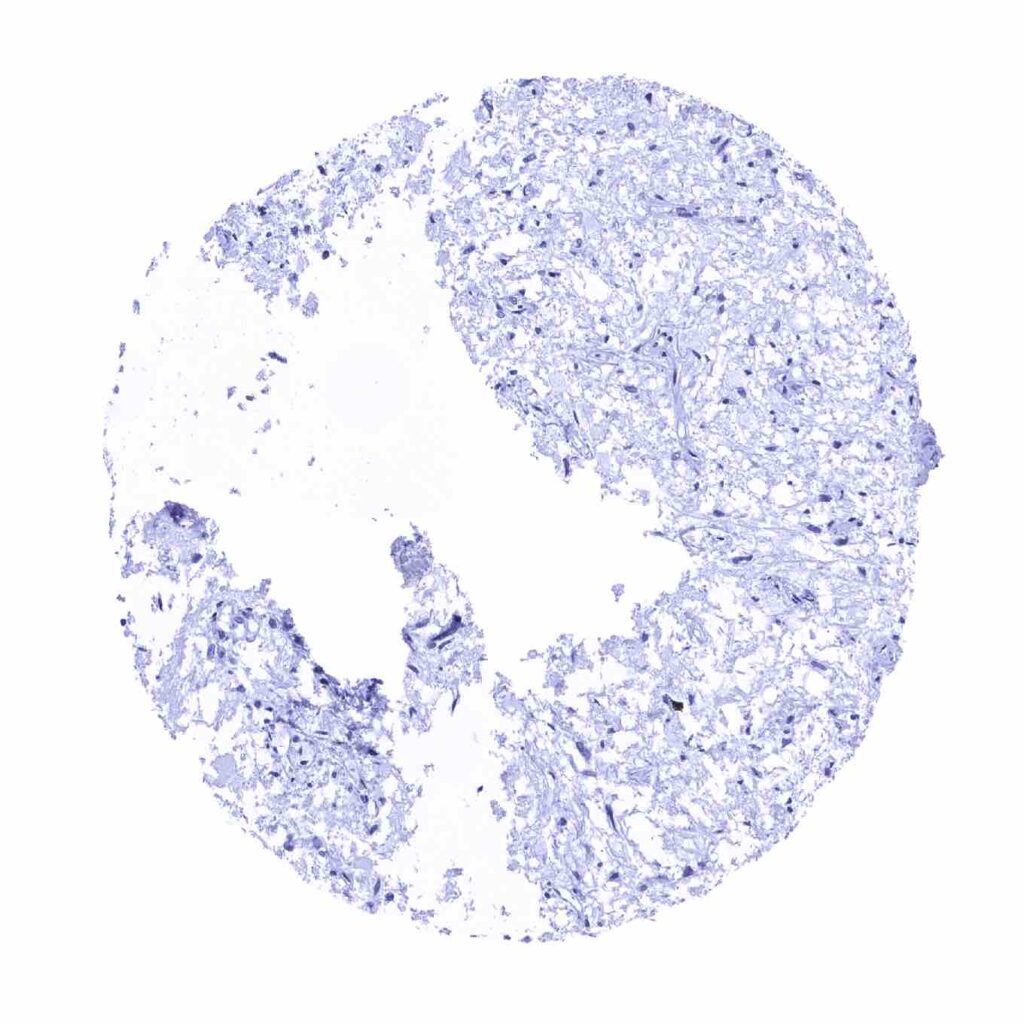

Lung